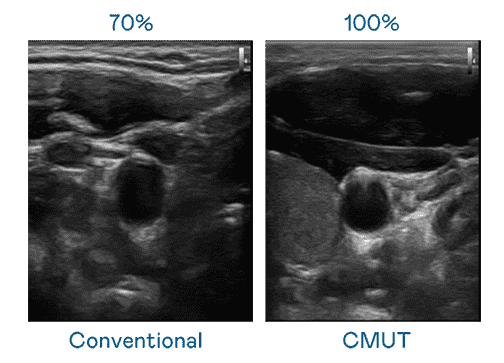

CMUT 技术是一种用电容式微机电元件来产生超音波讯号的技术。。与传统 PZT 压电式技术相比,,,,CMUT 频宽增加 30%,,更宽频的超音波讯号让影像解析度大幅提升,,,是实现高影像品质医疗超音波扫描、、、促进精准医疗发展的关键技术。。。。

大频宽带来超清晰影像

超音波影像的解析度高低,,首先取决于探头能发出的讯号频宽。。。。口袋牛店 CMUT 可提供高清晰的超音波讯号,,提供高频宽、、高灵敏度、、影像纹理细节更高的超音波影像,,,,协助医护人员缩短影像判读时间及利用精准的医疗影像进行诊断。。